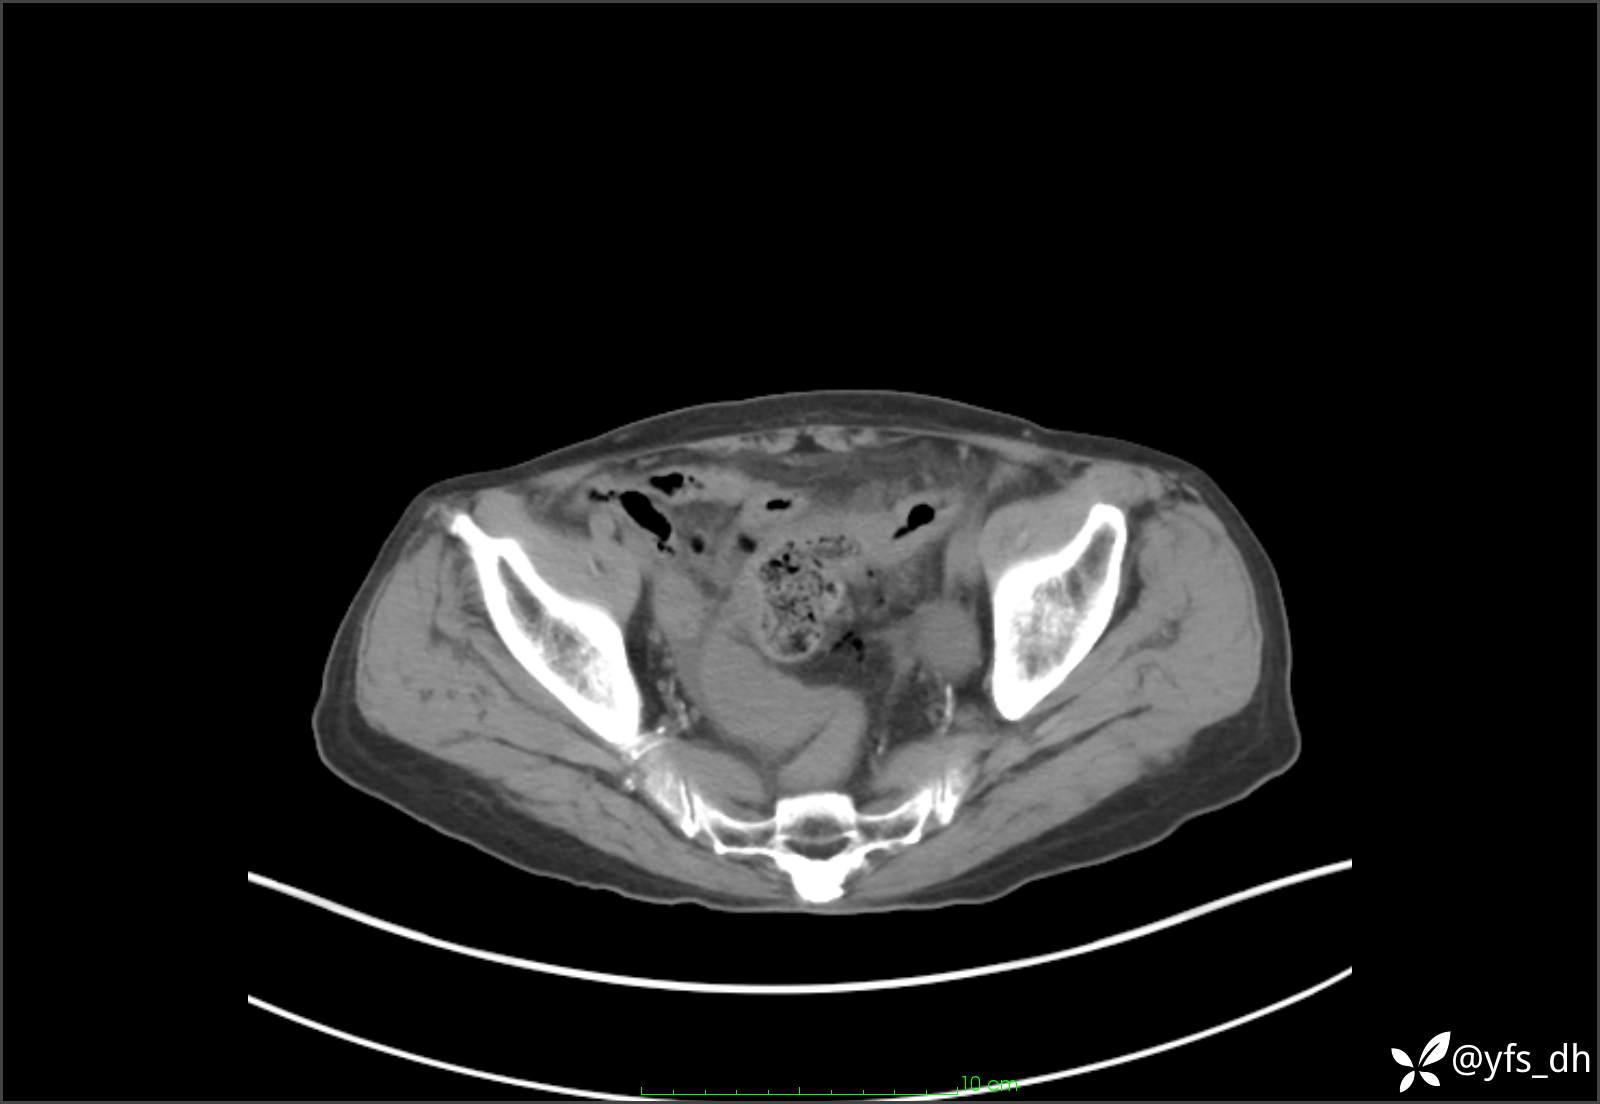

1.简要病史:患者4天前突发上腹部疼痛不适,但可以忍受。3小时前饭后突然加重,不能忍受后就诊。

2.简要手术记录:术中见腹盆腔大量肠液及粪便,乙状结肠中下段见一约3cm的破口。